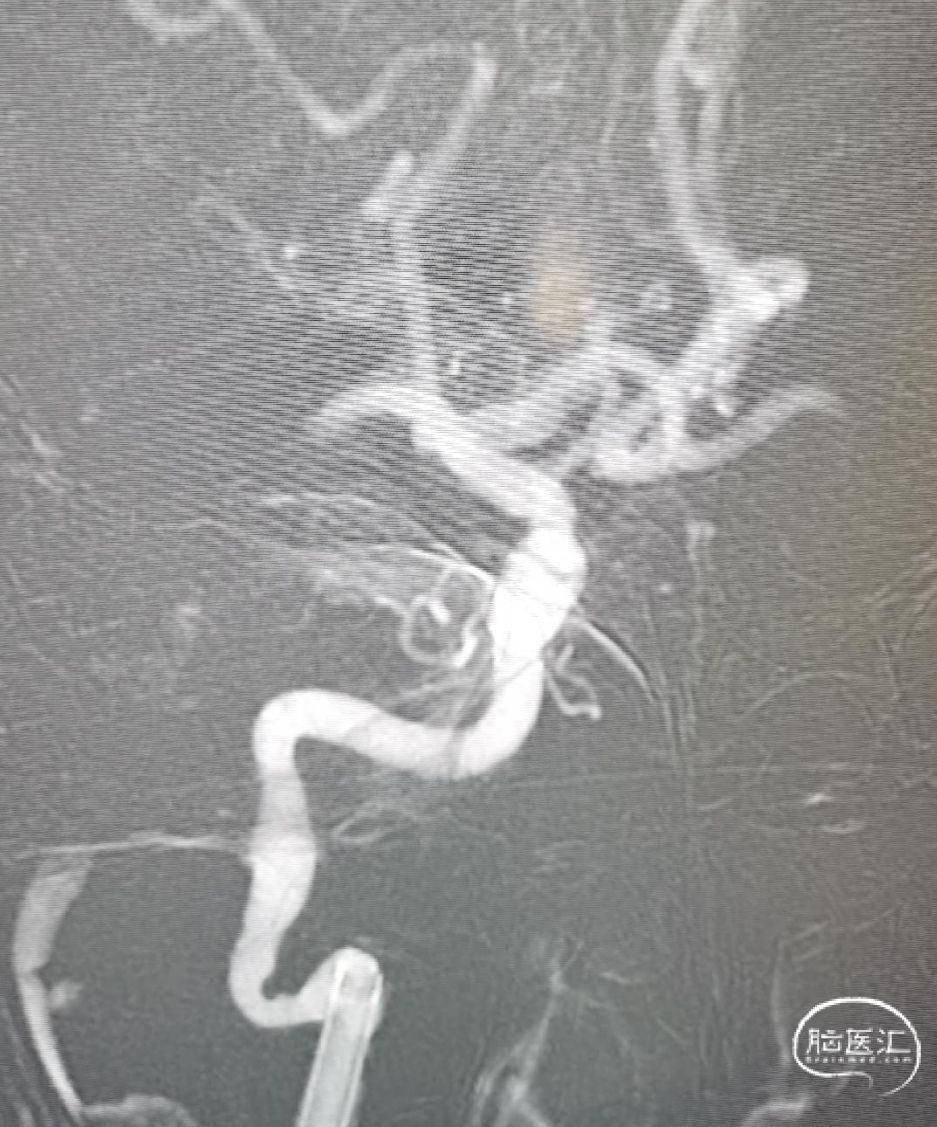

8F导引导管在多功能管及泥鳅导丝导引下直接进入右侧颈总动脉,此时Skathi远端通路导管尾端连接自制50ml负压注射器一路裸奔抽吸至C5段,反复抽吸3次,抽出大量血栓,回血通畅后,轻轻冒烟提示颈内动脉通畅,大脑中动脉M1远端闭塞,与取栓前后循环造影显示情况一致。

大脑中动脉M1段血栓采用SWIM技术-抽拉结合,避免血栓逃逸。

一次SWIM取栓,成功血管再通,达到mTICI分级:3级。